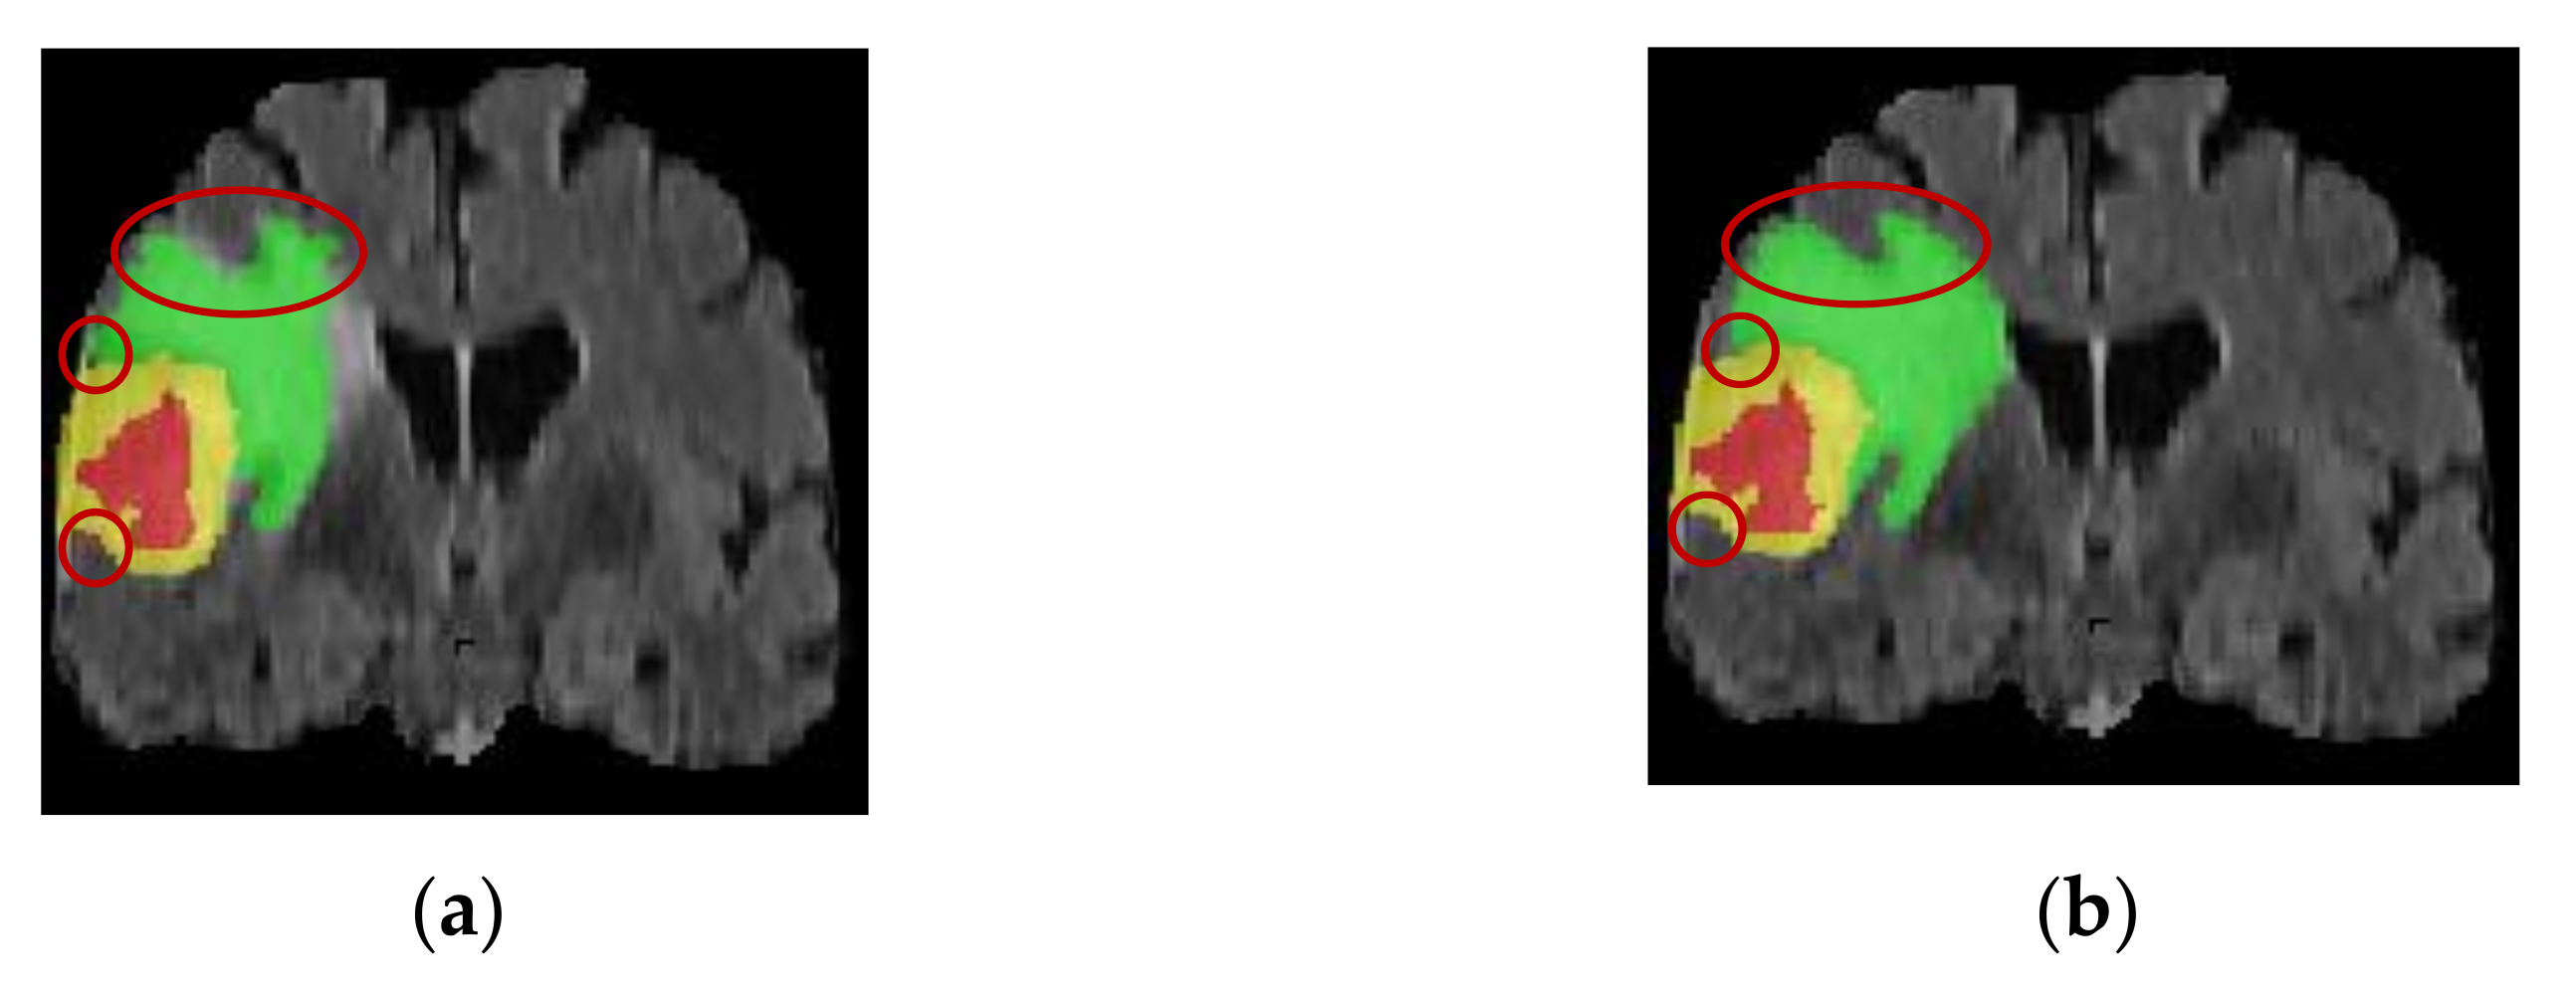

4.3.1. Analysis of the Visualization Results

- The 3D BCS hybrid domain attention mechanism module helps to improve the model’s recognition of the important feature information, and the residual connectivity enhances the segmentation ability. The hybrid loss function can further improve the segmentation accuracy of small targets and optimize the network performance.

- Our model has a low average deviation and a low dispersion, which allows for the further segmentation of the detailed contour of the model.

- In terms of the edge determination and accuracy of the ET and TC tumor areas, the model is superior to other SOTA models, which can help doctors accurately determine the precise location of the incision in surgery and protect patients’ healthy tissues from being removed.